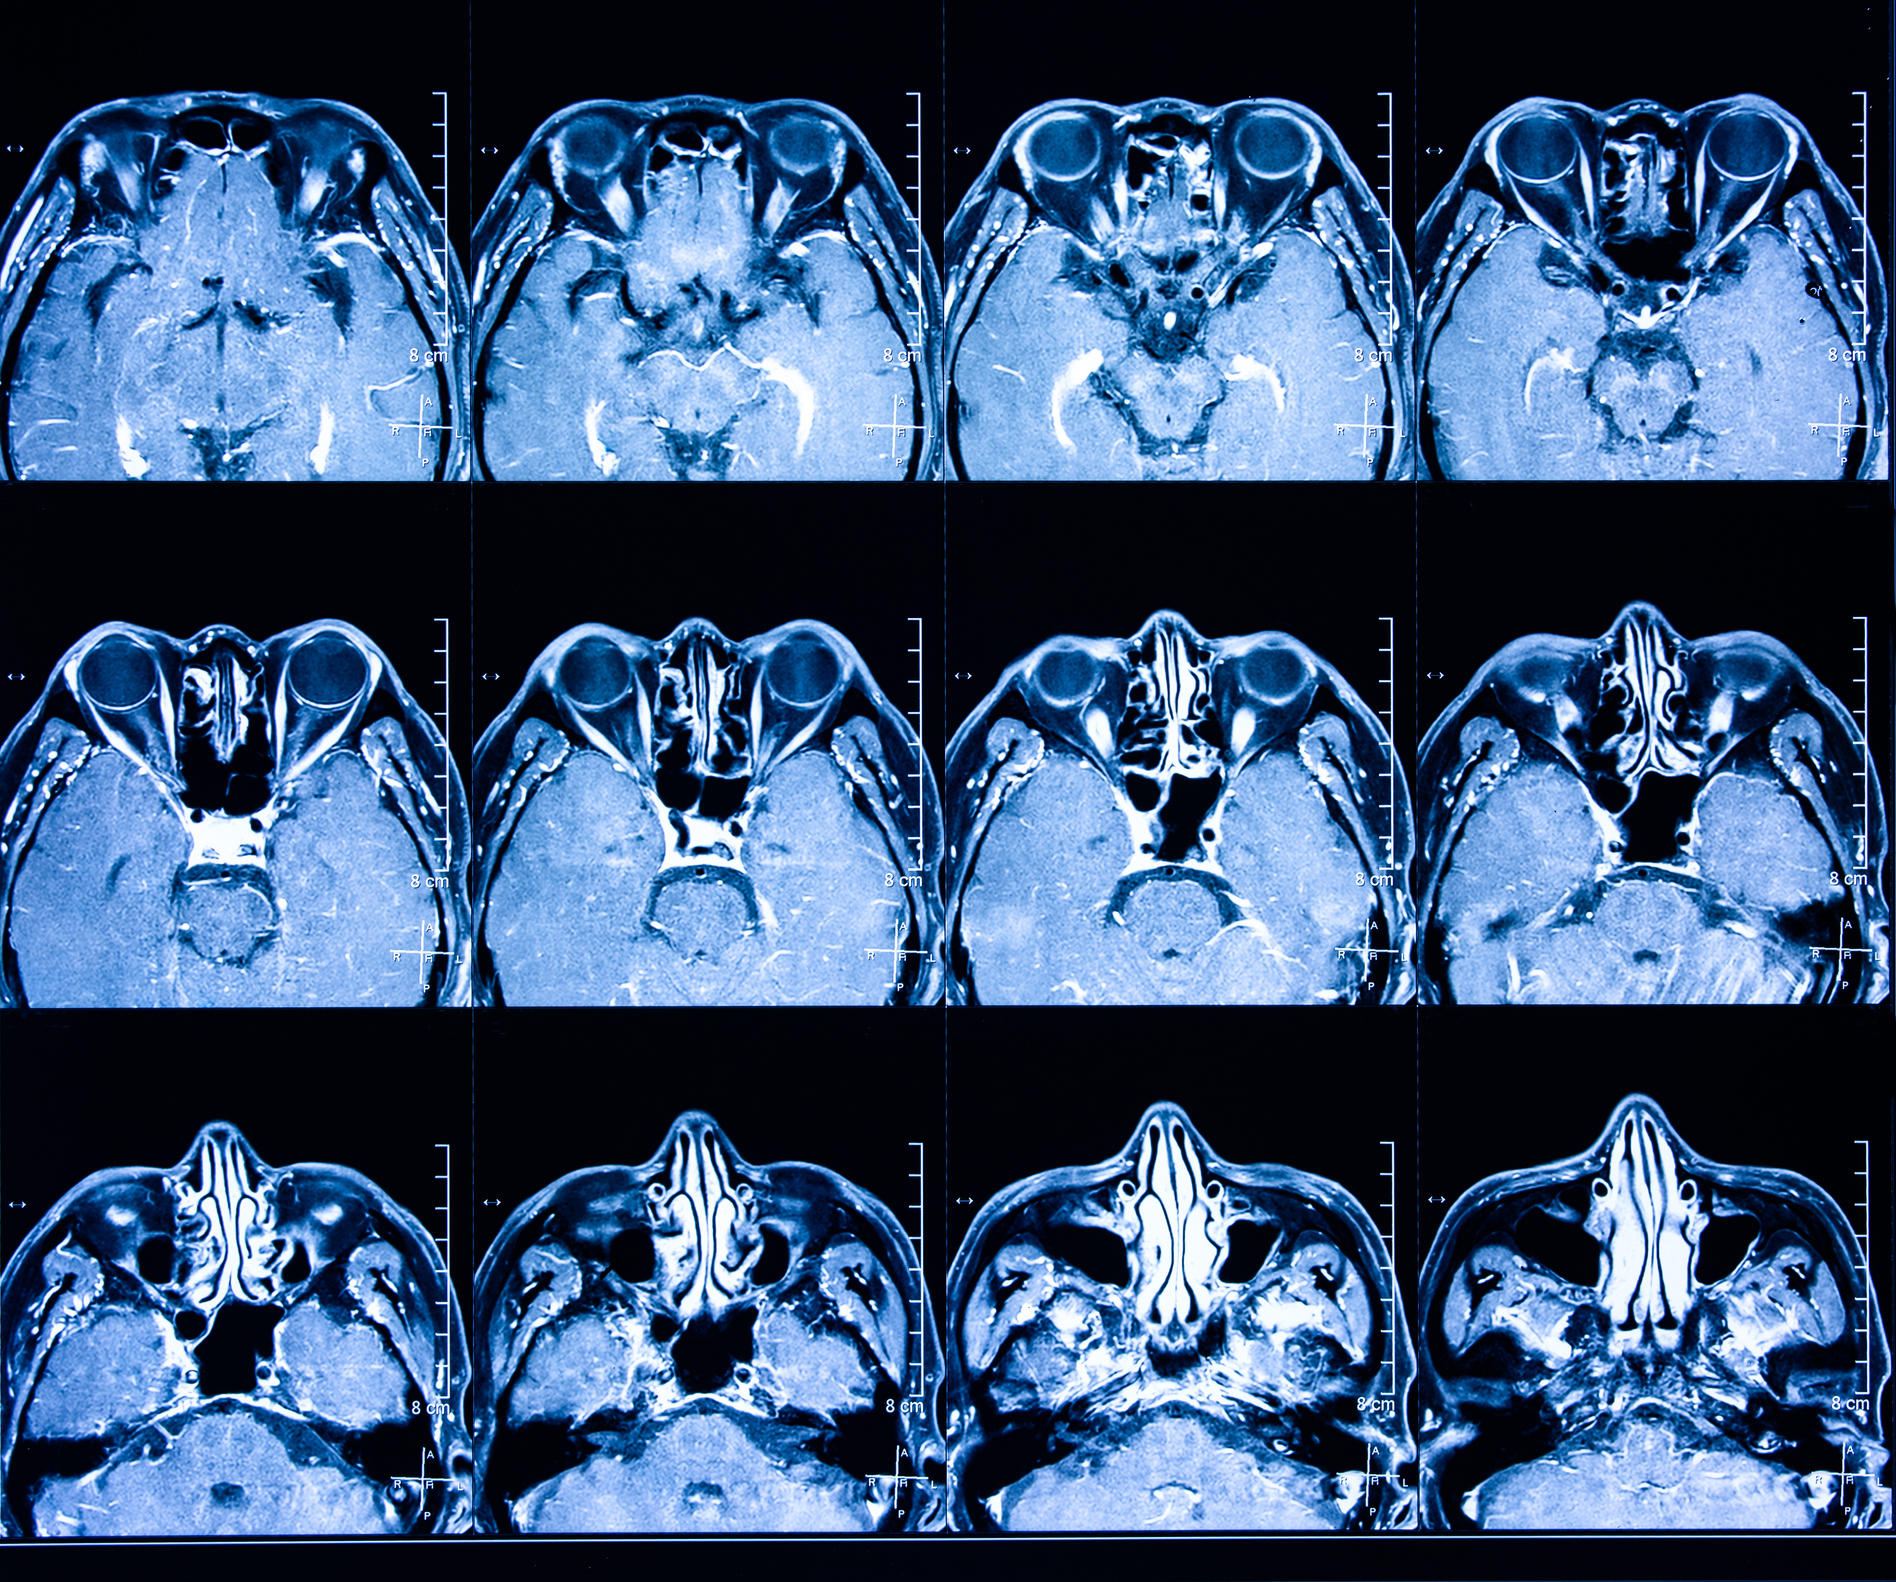

Paranasal Sinus and Nasal Cavity Cancer is a Head and Neck Cancer which occurs when the cells that form mucus within our nose and uppermost respiratory system turn cancerous.

‘Paranasal’ refers to an area around or near the nose, and there are several paranasal sinuses – the frontal sinus, the maxillary sinus, the ethmoid sinus, and the sphenoid sinus. Each of these hollow, air-filled structures are named according to the facial bones which surround them.

The area in which these cancers reside is quite sensitive, with many important nerves, blood vessels, and of course the eye, brain and carotid arteries which supply blood to the brain. Surgery needs to be planned very carefully, maintaining maximum function and appearance of these vital organs and structures. The extent of the surgery and any reconstruction options should be discussed with the treating doctor.

For cancers in the nasal cavity, a procedure called ‘wide local excision’ will be used to remove the tumour. An area of normal tissue around it will also be removed to ensure traces of the cancer are eliminated. Depending on whether the tumour is in the middle dividing wall of the nasal cavity (known as the nasal septum), or one of the lateral sides of the nose, surgeons will approach the cancer in different ways. Sometimes, the surgeon can reach the tumour by cutting into the upper lip as well.

Paranasal sinus cancers are more difficult to access. Depending on the size and location (which sinus areas are affected), the following operations may be used: